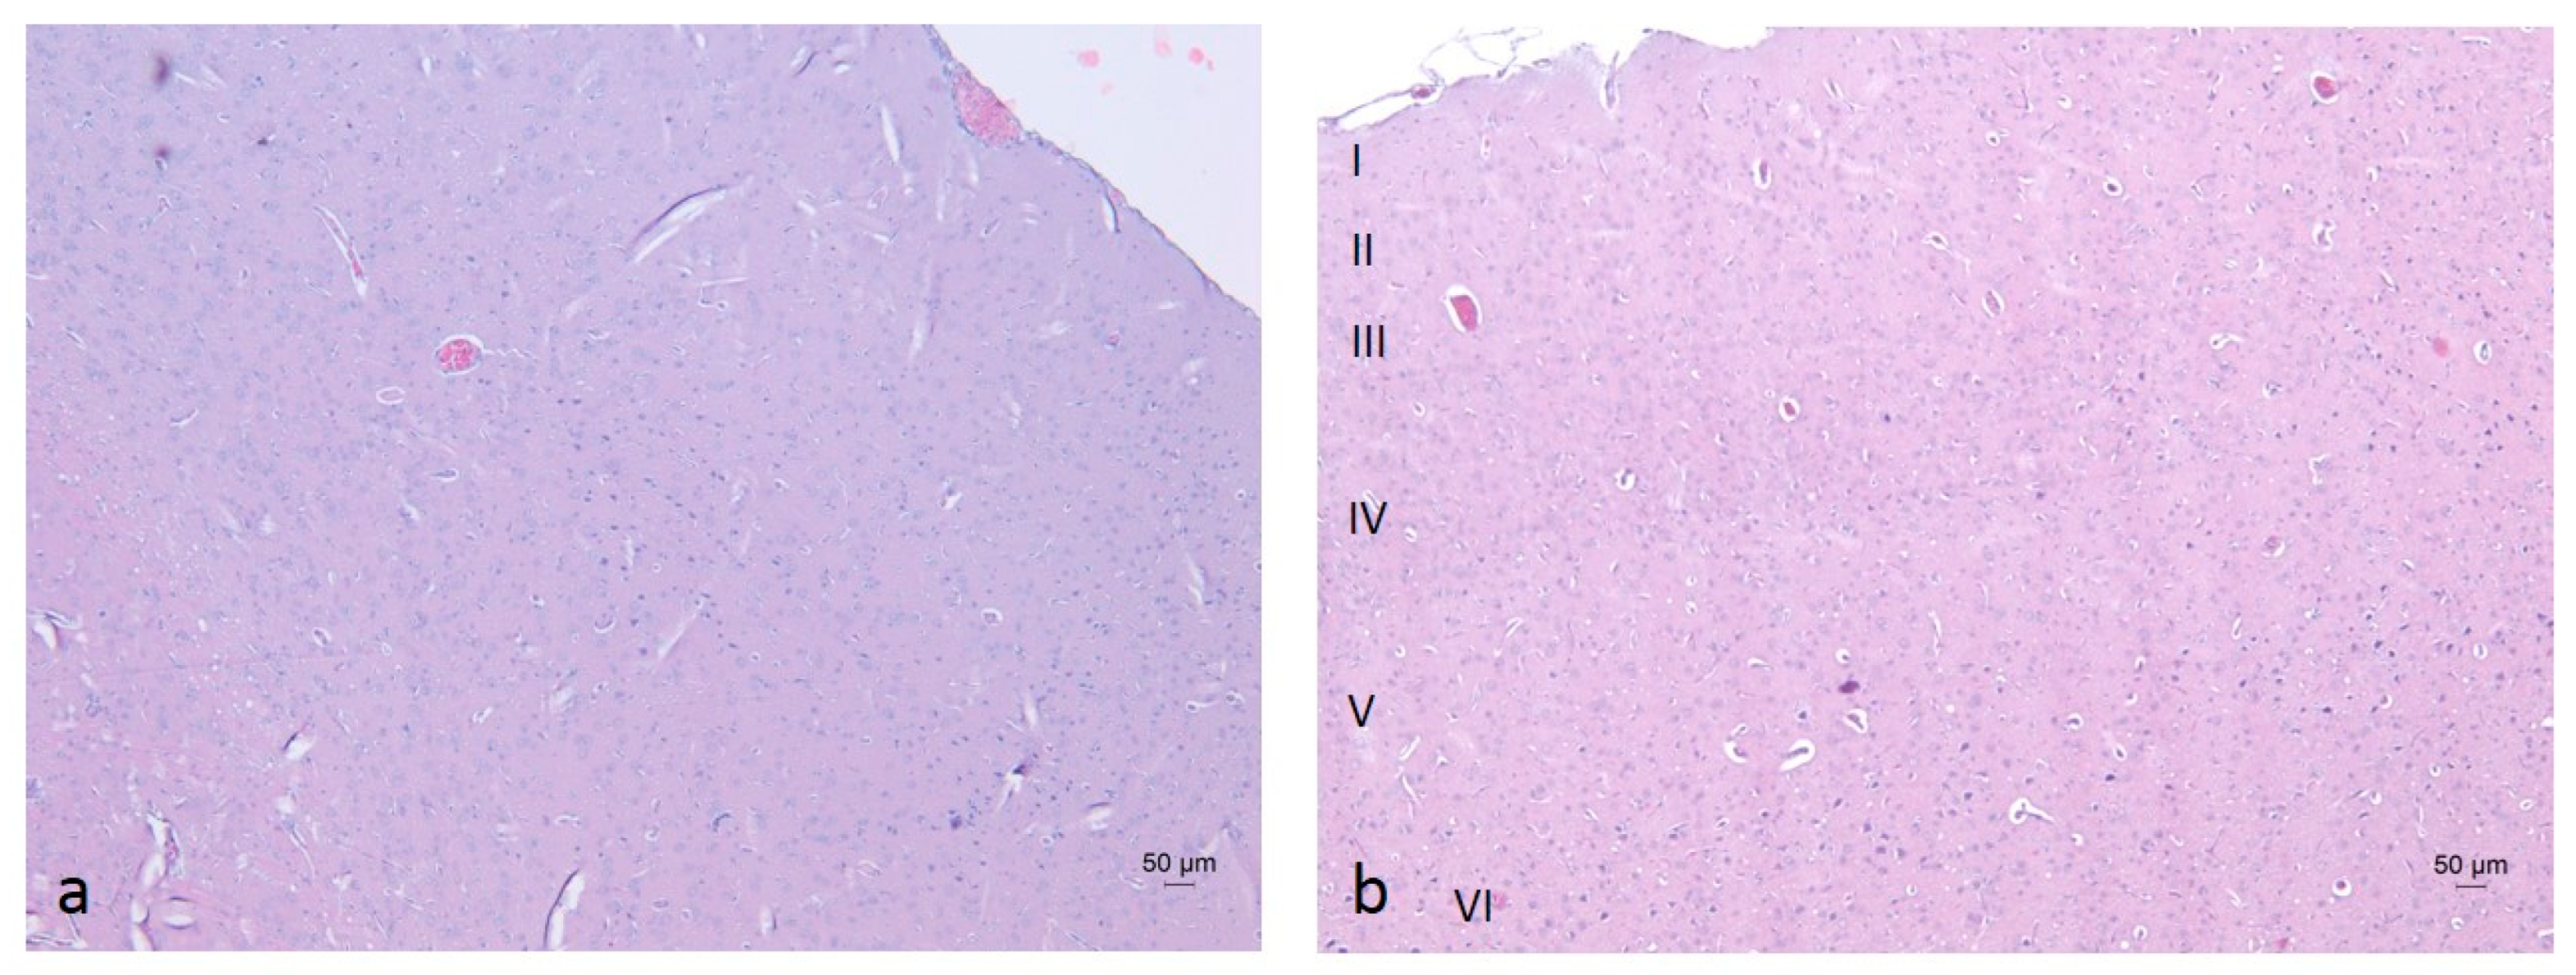

2.3. Histopathological Analysis of Brain Tissues

3.6. Histopathological Analysis

- Goulas, A.; Zilles, K.; Hilgetag, C.C. Cortical Gradients and Laminar Projections in Mammals. Trends Neurosci. 2018, 41, 775–788. [Google Scholar] [CrossRef]

- García-Cabezas, M.Á.; Zikopoulos, B.; Barbas, H. The Structural Model: A theory linking connections, plasticity, pathology, development and evolution of the cerebral cortex. Brain Struct. Funct. 2019, 224, 985–1008. [Google Scholar] [CrossRef] [PubMed]

| GROUP | PURKINJE CELL LOSS | NUCLEAR PYKNOSIS | MORPHOLOGICAL ALTERATIONS |

|---|---|---|---|

| Water–Saline (W-S) | - | - | - |

| Ethanol–Saline (E-S) | +++ | +++ | +++ |

| Ethanol–Memantine (E-M) | + | + | + |

| Ethanol–Rivastigmine (E-R) | ++ | ++ | + |

| Ethanol–ALA (E-A) | ++ | + | + |